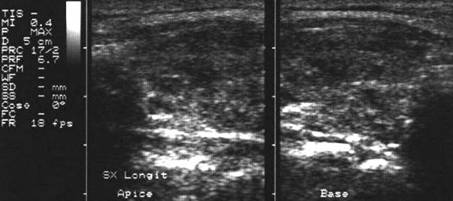

Femeie 25 ani. Nodul unic in lobul stang, contur net, hipoecogen, respecta parenchimul din jur, neomogen, de 18x23x36 mm (7,5 cc).

Citoaspiratia cu ac subtire: nodul adenomatos.

Examen histologic postoperator: adenom trabecular fetal.

Acelasi caz. La doppler color - vascularizatie interna, mai evidenta in powerdoppler.